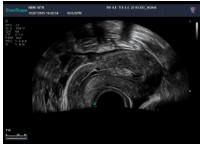

5腔內(nèi)探頭

腔內(nèi)探頭,具有頻率高,圖像分辨率高等特點(diǎn),不需充盈膀胱,探頭緊貼受檢部位,使盆腔器官處于聲束的近場區(qū)域,圖像更清晰。